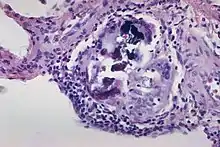

- ↑ USA, Yale Rosen from (2011-08-04), The crystalline inclusions that may be found within the giant cells in sarcoidosis and other granulomatous disorders consist mainly of calcium oxalate and well as some calcium cargbonate. In this image there are multiple Schaumann bodies closely associated with crystalline inclusions. In many cases the crystals appear to serve as a nidus around which Schaumann bodies are formed. H&E stain., retrieved 2021-12-10